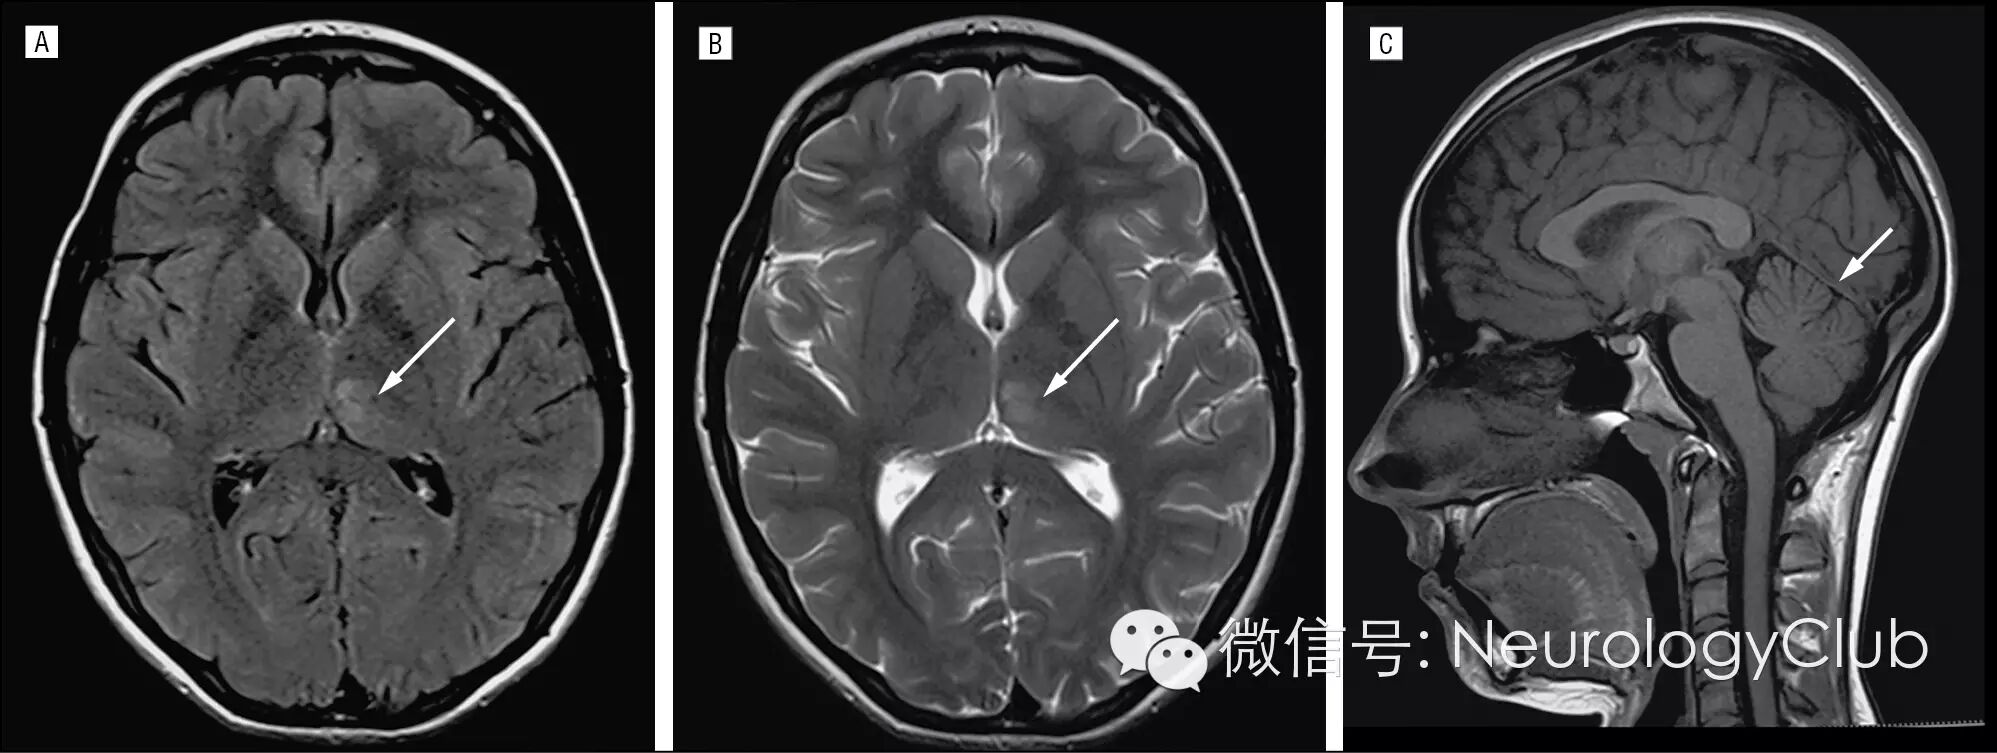

头颅MRI可见左侧丘脑病灶(图1AB)。磁共波谱分析(MRS)Cho/Cr比值下降(0.47),提示非炎性和非肿瘤性本质,同时伴有乳酸峰升高,符合厌氧糖酵解(图1C)。T1WI提示直窦和大脑内静脉血栓形成(图1D)。

(图1 A:FLAIR;B:T2WI;C:Cho/Cr值0.47;D:T1WI可见典型的直窦血栓形成征象)